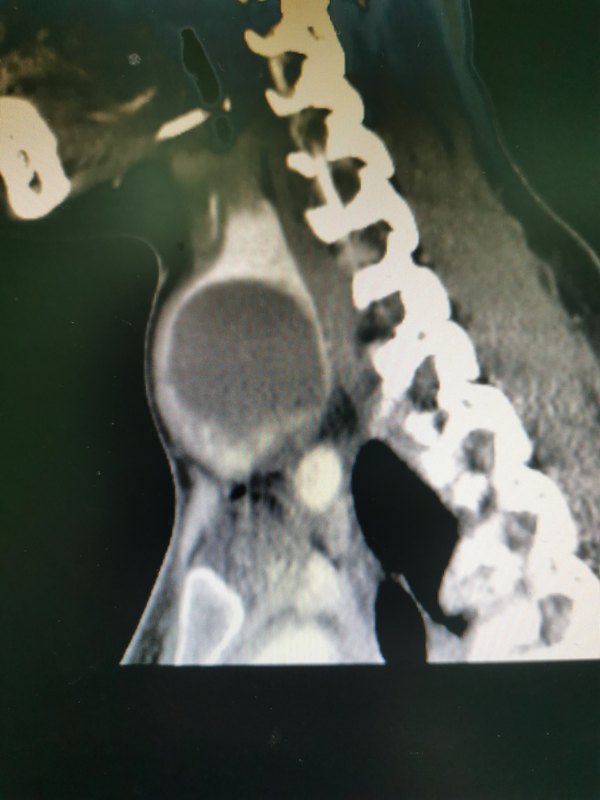

王女士,32歲,近2個月發(fā)現右側頸部包塊,緩慢長大,自覺吞咽不適,影響美觀。外院超聲檢查提示甲狀腺左側葉見一大小約4.2mm×3.5mm×95mm囊性為主的囊實性結節(jié)。王女士因治療后影響美觀而拒絕外科手術,經多方咨詢到介入科行DSA引導下經皮穿刺抽吸硬化治療。介入治療具有微創(chuàng)、安全、有效,術后不留癲痕,不影響甲狀腺功能,無須住院,費用低廉等優(yōu)勢,已成為治療這類疾病的主要方法。甲狀腺囊性病變患者一般無典型的癥狀,然而體積較大的囊腫病變常會出現出血,會對周圍產生壓力,引起聲音嘶啞、呼吸困難及咽部不適等癥狀,如不能進行及時治療,隨著病變的進一步進展,囊腫患者腫塊進一步的增大,對氣管造成壓迫甚至引起氣管軟化,這樣使得窒息發(fā)生,危及生命健康,因此對甲狀腺囊性病變,一旦檢出需要進行科學有效的治療。

經過1年的臨床實踐,我治療組針對單側單發(fā)良性較大腫物應用特殊手術技巧將腫物剝除,術后6個月內復查甲功七項和超聲檢查,結果提示手術前后甲狀腺功能對比無顯著性差異,術前超聲提示正常甲狀腺組織被腫物壓迫體積縮小,術后3~6個月復查超聲提示與對側正常甲狀腺體積相比,病變側甲狀腺體積幾乎恢復正常大小。為微創(chuàng)手術最小化切除腫物的手術方式的優(yōu)選,其遠期療性觀察中。手術適應癥1.術前經超聲檢查證實為單發(fā)囊性腫物,最大徑超過4.0cm,不超過6.0cm2.患側腺體沒有其他超聲可見結節(jié)性病變3.對側腺體沒有其他超聲可見結節(jié)性病變或無最大徑超過1.0cm的良性腫物

囊腫,顧名思義,就是一個囊狀的物體局部突起,形成包塊,內容物常為液體滲出。氣球,大家都玩過吧,里面加點水,局部加壓擠出來一個小球樣的突起,這就是囊腫。囊腫可以長在體表,也可以長在內臟,如“甲狀腺囊腫”、“肝囊腫”、“腎囊腫”、“卵巢囊腫”等,因為屬于良性疾病,基本不會癌變,所以小囊腫一般都不需要處理,每年定期檢查就行。但如果囊腫增大到一定程度,如直徑超過5cm則破裂風險較大,或者囊腫增大對周圍組織產生了壓迫,出現臨床不適癥狀,如腰酸、腹痛等,則需要進行干預治療了。囊腫的治療大致有3種,傳統(tǒng)外科手術切除、微創(chuàng)腔鏡開窗和介入穿刺抽吸硬化。傳統(tǒng)外科手術切除因為創(chuàng)傷大,基本已經淘汰。微創(chuàng)腔鏡開窗是通過腔鏡技術,在囊腫表面挖一個洞,讓囊液自己慢慢流出來然后機體吸收,創(chuàng)傷小了,但復發(fā)率較高,部分病人囊液外流也會造成組織感染。介入穿刺抽吸硬化,則是既有微創(chuàng)的優(yōu)點,又可避免高復發(fā)的風險。它是通過B超或CT引導,把一根細針穿刺進入囊內,針尾外界注射器抽吸干凈囊液,然后將無水酒精注射入囊內破壞囊壁分泌旺盛的細胞,這樣可以最大程度的減少復發(fā),整個治療過程創(chuàng)傷只有一個針眼。